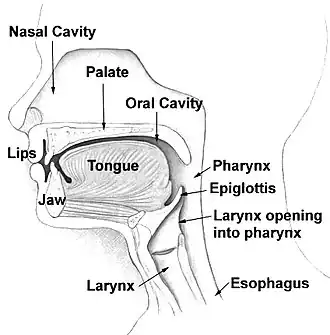

- difficulty chewing or dysphagia

- speech difficulties, such as slurred speech (due to the tongue being affected)

During a routine exam, the dentist may be able to diagnosis this condition through a visual examination by inspecting the mouth for any irregularities such as bony growths. The dentist during this visual exam will focus on the palate, lingual side of the lower jaw, and the outer areas of the upper and lower jaws. Once visual examination indicates an oral torus, the dentist will then feel for palpation in the suspect area in order to further examine the size, shape, and firmness of the oral tori. Though imaging is not necessary to diagnose oral tori, the dentist may decide to do imaging to rule out cysts or tumors (which may cause similar symptoms or have similar factors) by taking an x-ray (for a 2D view) or CT scan (for a 3D view) of the mouth to get a better view of the exact size and location of the growth.[13]